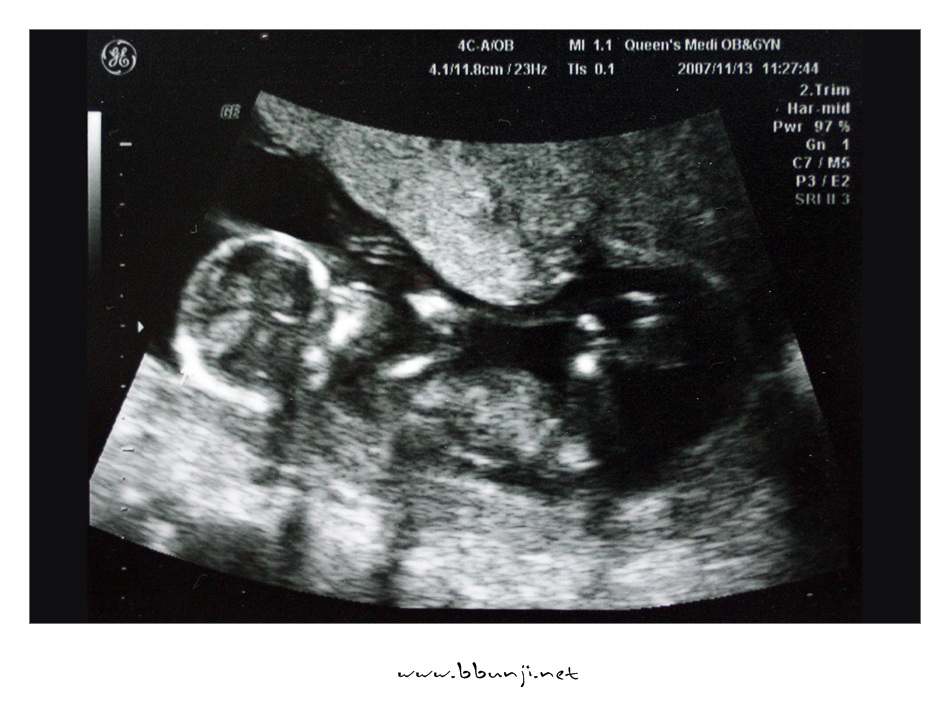

사랑이… 14주 째.. *^^*

2007년 11월 13일

이제 우리 사랑이 제법 키가 커서 8cm가 다 되었습니다.

배초음파를 하는데 첨에는 손깍지 끼고 다리 오므리고 있다가 팔도 움직이고 다리도 움직이더라구요.

이제 척추랑 갈비뼈도 완전히 보이고 손모양도 얼추 제법 모습이 보이네요.

의사 선생님이 코가 오똑하답니다.ㅋㅋㅋ

그 작은 것이 꼬물거리고 심장이 뛰는거 보니 희안하다 못해 신비하기까지 합니다.